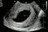

Inilah ultrasound scan rahim ibu yang sudah hamil hampir 3 bulan. Di dalam rahimnya ada kantung kehamilan yang mengandungi air ketuban (air akan kelihatan hitam melalui imbasan ultrasound scan), tetapi tiada janin yang terbentuk di dalam kantungnya. Dari permulaan kehamilan lagi memang tidak ada janin. Inilah yang dinamakan kehamilan tanpa embryo, atau anembryonic pregnancy. 40% wanita yang mengalami keguguran ada kehamilan tanpa embryo. Ada ramai juga yang walaupun ada pembentukan janin, tetapi janin itu tidak normal dan gugur. Sebabnya ialah terdapat kerosakan baka DNA kepada benih telur atau sperma, yang apabila dipersenyawakan tidak boleh menjadi. Walaupun kita manusia yang sihat, bukan semua benih kita sempurna. Tetapi, banyak kes sebegini, keguguran tidak selalunya berlaku dengan serta-merta, sebab itulah bila kita buat ultrasound scan 8 minggu sehingga 12 minggu kehamilan, kantungnya sudah besar tetapi kosong, dan keguguran masih belum berlaku. Pada hakikatnya, untuk kehamilan yang sihat, kita sudah boleh melihat janin terbentuk melalui ultrasound scan sejak 5-6 minggu kehamilan lagi dan boleh lihat denyutan nadi jantung janin. Sudah terlalu banyak kali, saya jumpa kes sebegini bila ibu-ibu hamil datang ke klinik berjumpa dengan saya. Kebanyakannya akan mengalami keguguran dengan sendirinya sebelum 3 bulan. Mereka datang ke klinik untuk ultrasound scan kerana sudah mula melihat sedikit pendarahan menandakan proses keguguran sudah bermula. Mereka tanya saya, adakah sebabnya mereka makan buah nenas semalam, adakah sebabnya mereka minum air kelapa minggu lepas, adakah sebabnya mereka minum air tebu bulan lepas. Adakah sebabnya mereka angkat benda berat pagi ini. Adakah rahim tidak kuat. Jawapan saya ialah TIDAK, Puan. Puan tidak bersalah. Tiada makanan yang menyebabkan masalah ini, dan kegiatan fizikal anda tidak menyebabkan masalah ini. Ini bukan sebab rahim tidak kuat. Sebab itulah saya kata, jangan salahkan diri sendiri. Sebab itulah saya berkata kepada semua orang lain, jangan mencari kesalahan wanita yang mengalami keguguran. Jangan buat fitnah kepada buah nenas. Pada hakikatnya, sudah memang pun kehamilan itu tidak boleh menjadi, sebelum ibu itu makan buah nenas lagi. Banyak penjelasan yang saya sudah sampaikan dalam program #TanyaDrImelda Episod 3, tentang keguguran dan kenapa ia berlaku.